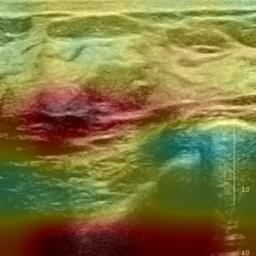

Ultrasonography is an important routine examination for breast cancer diagnosis, due to its non-invasive, radiation-free and low-cost properties. However, it is still not the first-line screening test for breast cancer due to its inherent limitations. It would be a tremendous success if we can precisely diagnose breast cancer by breast ultrasound images (BUS). Many learning-based computer-aided diagnostic methods have been proposed to achieve breast cancer diagnosis/lesion classification. However, most of them require a pre-define ROI and then classify the lesion inside the ROI. Conventional classification backbones, such as VGG16 and ResNet50, can achieve promising classification results with no ROI requirement. But these models lack interpretability, thus restricting their use in clinical practice. In this study, we propose a novel ROI-free model for breast cancer diagnosis in ultrasound images with interpretable feature representations. We leverage the anatomical prior knowledge that malignant and benign tumors have different spatial relationships between different tissue layers, and propose a HoVer-Transformer to formulate this prior knowledge. The proposed HoVer-Trans block extracts the inter- and intra-layer spatial information horizontally and vertically. We conduct and release an open dataset GDPH&GYFYY for breast cancer diagnosis in BUS. The proposed model is evaluated in three datasets by comparing with four CNN-based models and two vision transformer models via a five-fold cross validation. It achieves state-of-the-art classification performance with the best model interpretability.

翻译:超声波分析是乳腺癌诊断的一个重要常规检查,原因是其非侵入性、无辐射和低成本的特性。然而,由于其内在局限性,它仍不是乳腺癌的第一线筛选测试。如果我们能够精确地通过乳房超声图像诊断乳腺癌(BUS),它将是一个巨大的成功。我们提出了许多基于学习的计算机辅助诊断方法,以实现乳腺癌诊断/感官分类。然而,其中多数方法需要事先确定性能模型,然后对ROI内部的跨值进行分类。常规分类支柱,如VGG16和ResNet50等,可以在没有ROI要求的情况下实现有希望的分类结果。但是这些模型缺乏可解释性,从而限制了其在临床实践中的使用。在本研究中,我们提出了一个新的无乳腺癌诊断模型,在超声波图像中进行解释性特征描述。我们利用了先前的解剖学学学知识,即恶性肿瘤和良性肿瘤模型在不同组织层之间有着不同的空间关系,并提议采用状态解析法来编制这一先前的知识。拟议中的HOVer-Trans-Trading-Tradef-trainal Ex-deal-dealal-deal-deal-deal-degraphal-deal-deal-deal-deal-deal-deal disal disal-dal-dal-dal-dal-dal-deal-deal-dal-deal-deal-deal-dal-dal-dal-dal-dal-dal-dal-dal-dal-dal-dal-dal-dal-dal-I-dal-Iversal-dal-Ial-d-d-I-d-d-I-I-I-I-I-I-I-I-I-I-I-I-I-I-I-I-I-I-I-I-I-I-I-I-I-Ial-I-Ial-Ial-I-I-I-I-I-I-I-I-I-I-I-I-I-I-I-I-I-I-I-I-I-I-I-I-I-I-I-I-I-I-I-I-